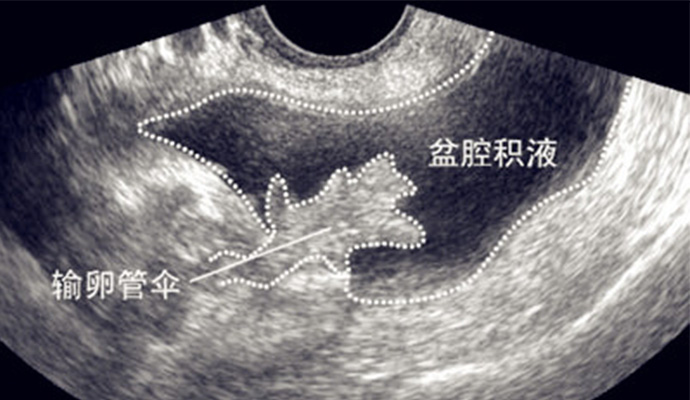

盆腔積液一種很常見的盆腔疾病,大部分的女性朋友月經(jīng)前后以及排卵期內(nèi)盆腔都會有少量的血液,形成盆腔積液的癥狀,但這些都是生理性的,很快就可以自行恢復。而病理性的盆腔積液就是身體的炎癥反應了,必須要積極治療,那盆腔積液都有哪些癥狀表現(xiàn)呢?

盆腔積液的患者會出現(xiàn)月經(jīng)和白帶異常的情況,盆腔內(nèi)有積液時有可能會造成盆腔淤血,盆腔淤血出現(xiàn)會對盆腔的正常功能產(chǎn)生一定的影響,這樣就會導致女性的月經(jīng)出現(xiàn)紊亂,白帶也會出現(xiàn)異常。另外,盆腔積液還會給女性的卵巢帶來很大的影響,這樣會使女性的月經(jīng)功能出現(xiàn)異常。

女性患有盆腔積液很多時候是由于之前所患的一些慢性炎癥出現(xiàn)了疤痕、粘連等情況引起的,這樣一來女性的盆腔就會出現(xiàn)充血的情況,盆腔充血是很容易引起腹部疼痛的,主要就是下腹疼痛。另外,女性患上盆腔積液還有可能會堵塞輸卵管,輸卵管如果堵塞就很容易發(fā)生不孕不育的可能。